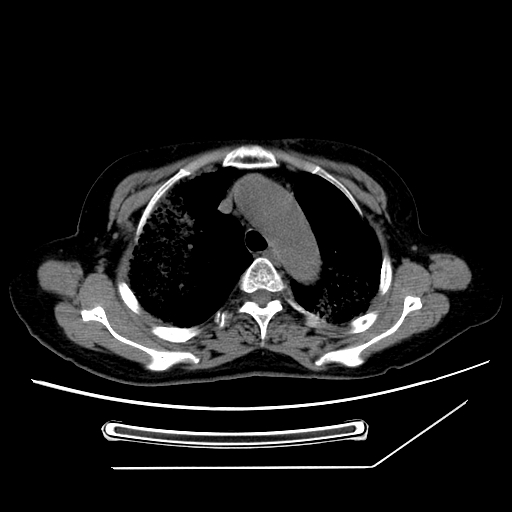

标题: CT25393:病人45岁,咳嗽,吐黄痰带血丝,发热,胸闷月余 [打印本页]

标题: CT25393:病人45岁,咳嗽,吐黄痰带血丝,发热,胸闷月余

1、左肺中央型肺癌并双肺弥漫性转移   2、双肺部感染    3、肺大泡     4、左侧胸腔积液

双侧肺弥漫性病变,可见“空泡征”及“蜂窝征”,考虑肺泡癌可能性大,左侧胸腔积液,考虑胸膜受累可能!

考虑肺泡癌,建议排除感染。

考虑肺泡癌

1)不排除肺泡癌可能。2)左侧胸腔积液。